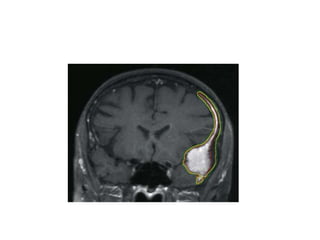

MRI

• MRI is the investigation of choice for the diagnosis and

characterization of meningiomas.

• When appearance and location is typical, the diagnosis can be made

with a very high degree of certainty.

• Typically appear as extra-axial masses with a broad dural base. They

are usually homogeneous and well circumscribed.

Frontal view at MRI of a typical convexity

meningioma

The scans below show a patient with meningioma

The scans below show the same patient with meningioma SIX

The scans belowshow a patient with meningioma The scans below show the same patient with meningioma SIX MONTHS after gamma knife treatment.